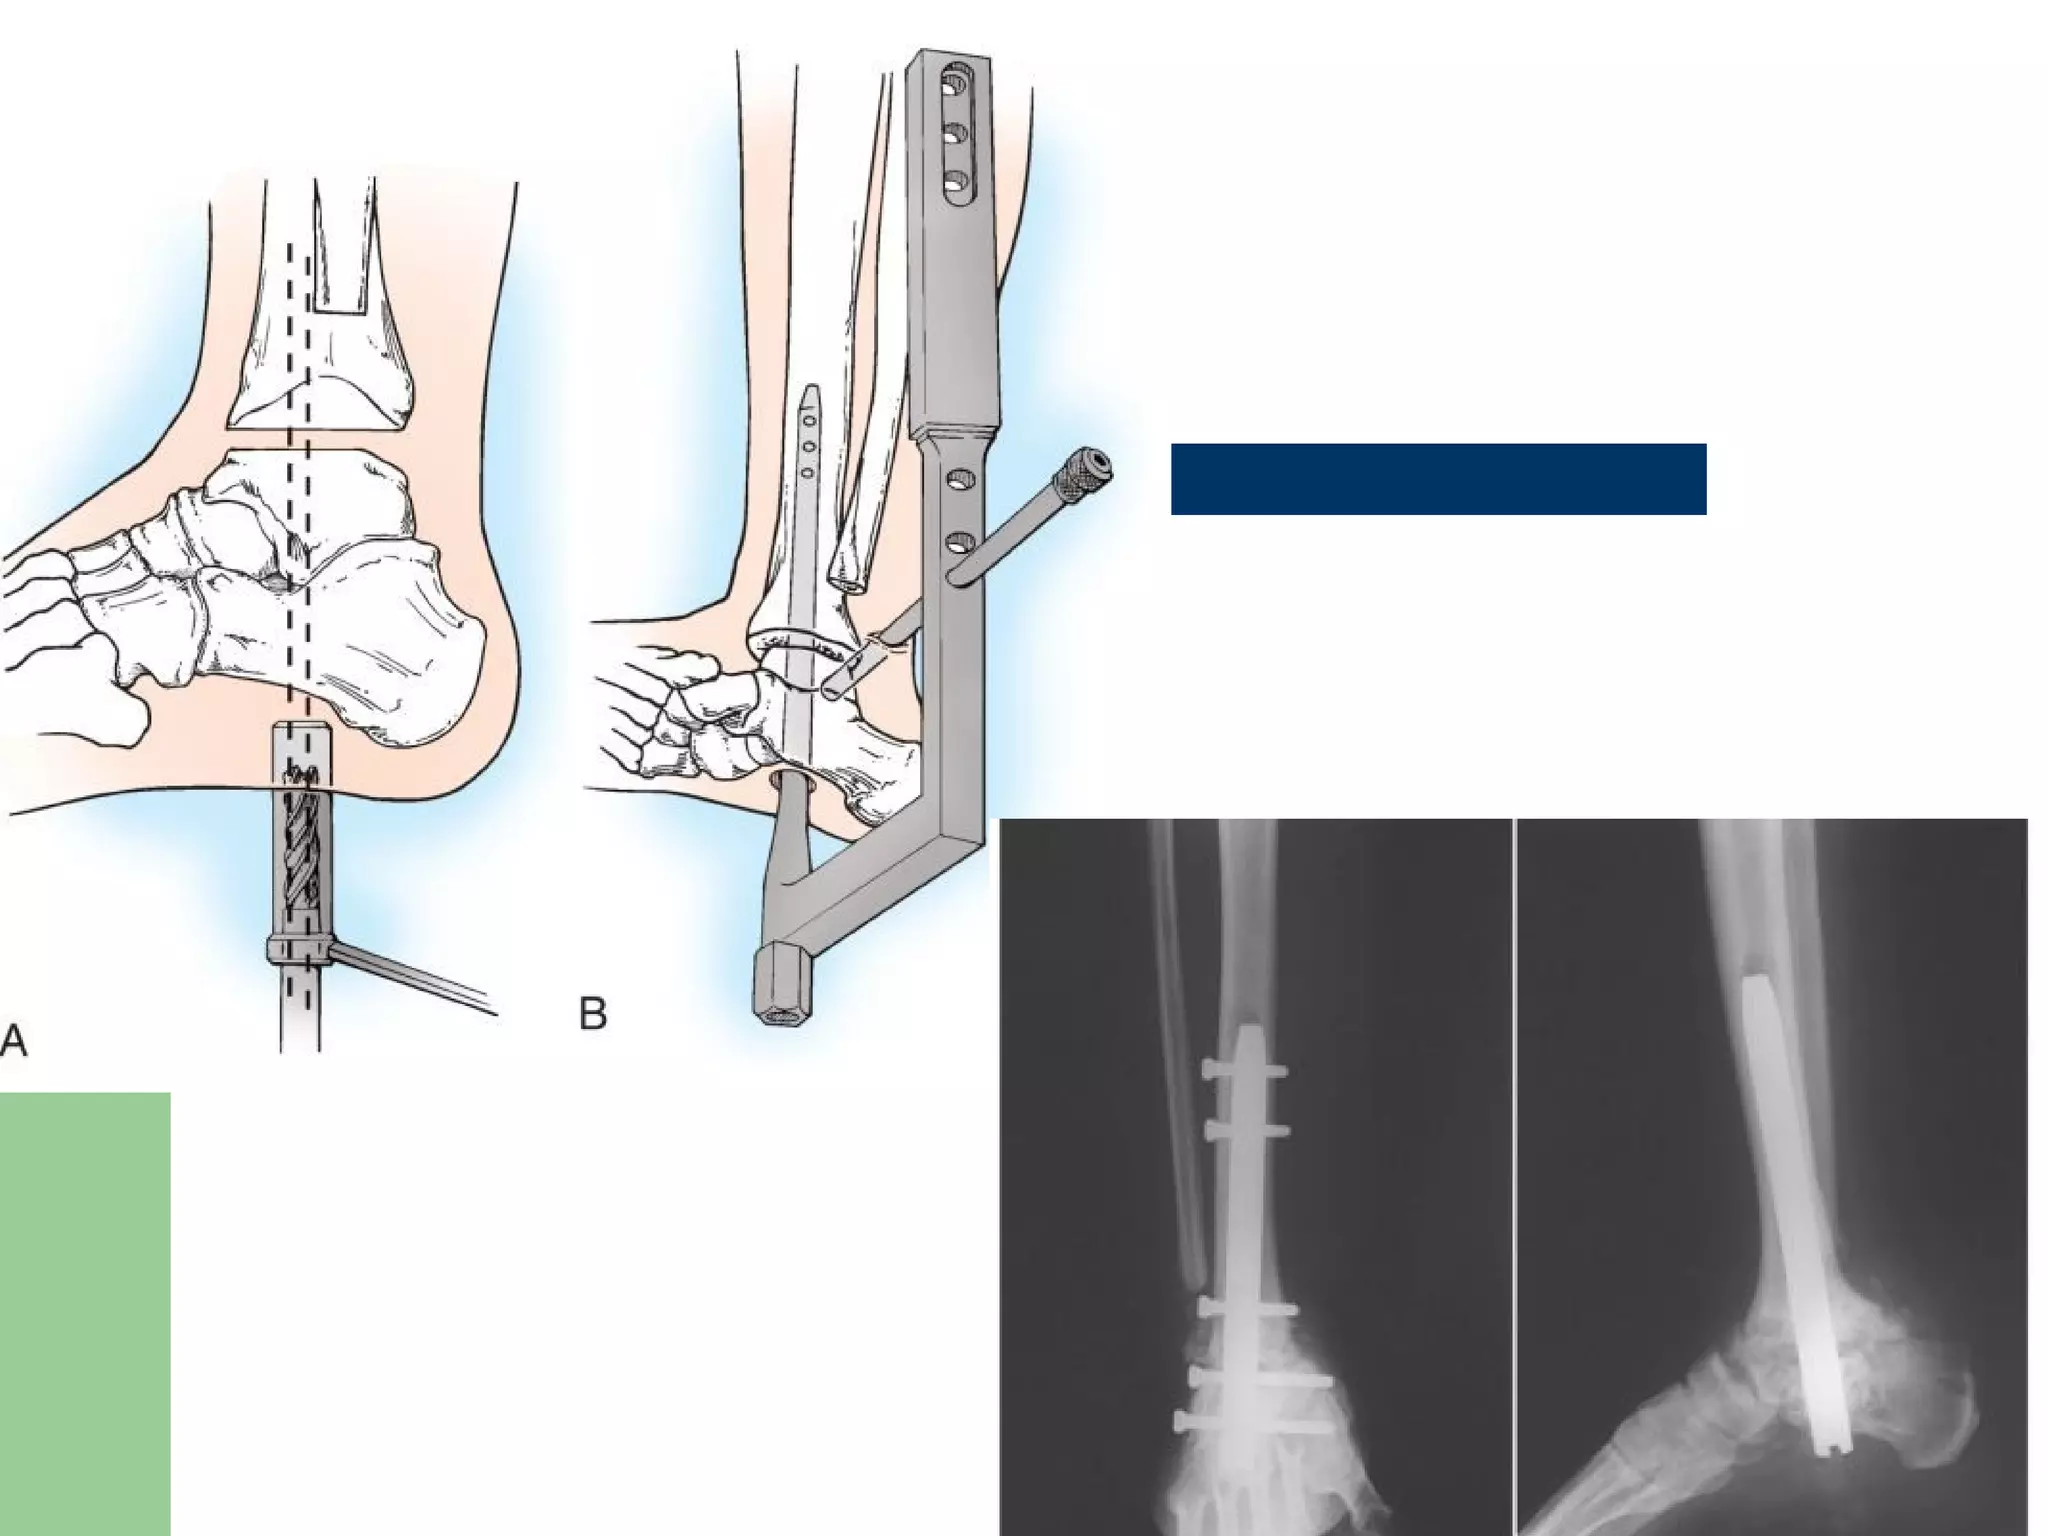

Surgical treatment Ankle:  Arthrodesisof ankle to place the foot Plantigrade.  IM nail/Charnley/Ilizarov External Fixators  Average time for Fusion:20 months(IM nail).  Talus -- fragmented and avascular--talectomy and tibiocalcaneal arthrodesis.

• 68.